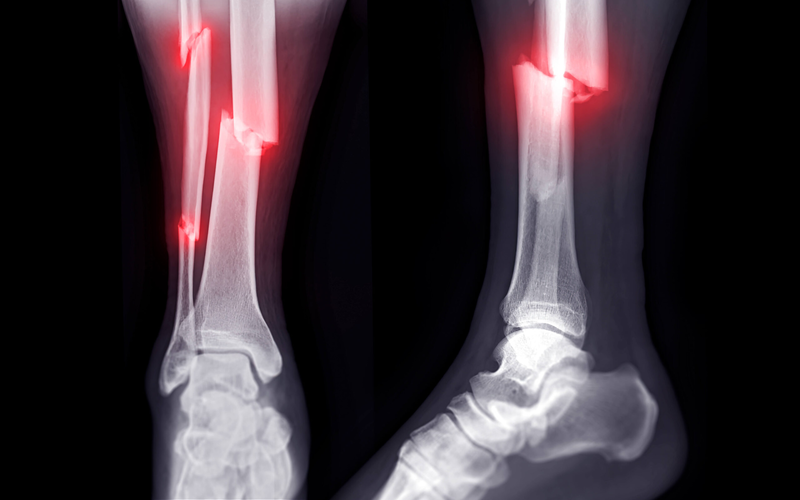

Fractures of the foot and ankle range from small stress fractures to severe traumatic breaks. Dr. Storts provides comprehensive fracture care with on-site X-rays for quick, accurate diagnosis.